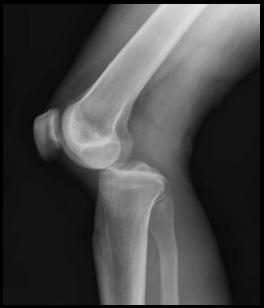

X-ray of dislocated knee Source: Duprey K, Lin M. Posterior knee dislocation. West J Emerg Med. 2010;11(1):103-104.

In the x-ray image above, we see a posterior dislocation at the knee. This injury can be induced by a strong thrust or kick to the anterior surface of the knee joint at or below the patella which is at the junction of the femur and the tibial bone. A dislocation of this severity and degree will completely shear and detach the ligaments of the knee. Such an injury will result in extreme pain and an inability to bear weight on the joint or the leg.